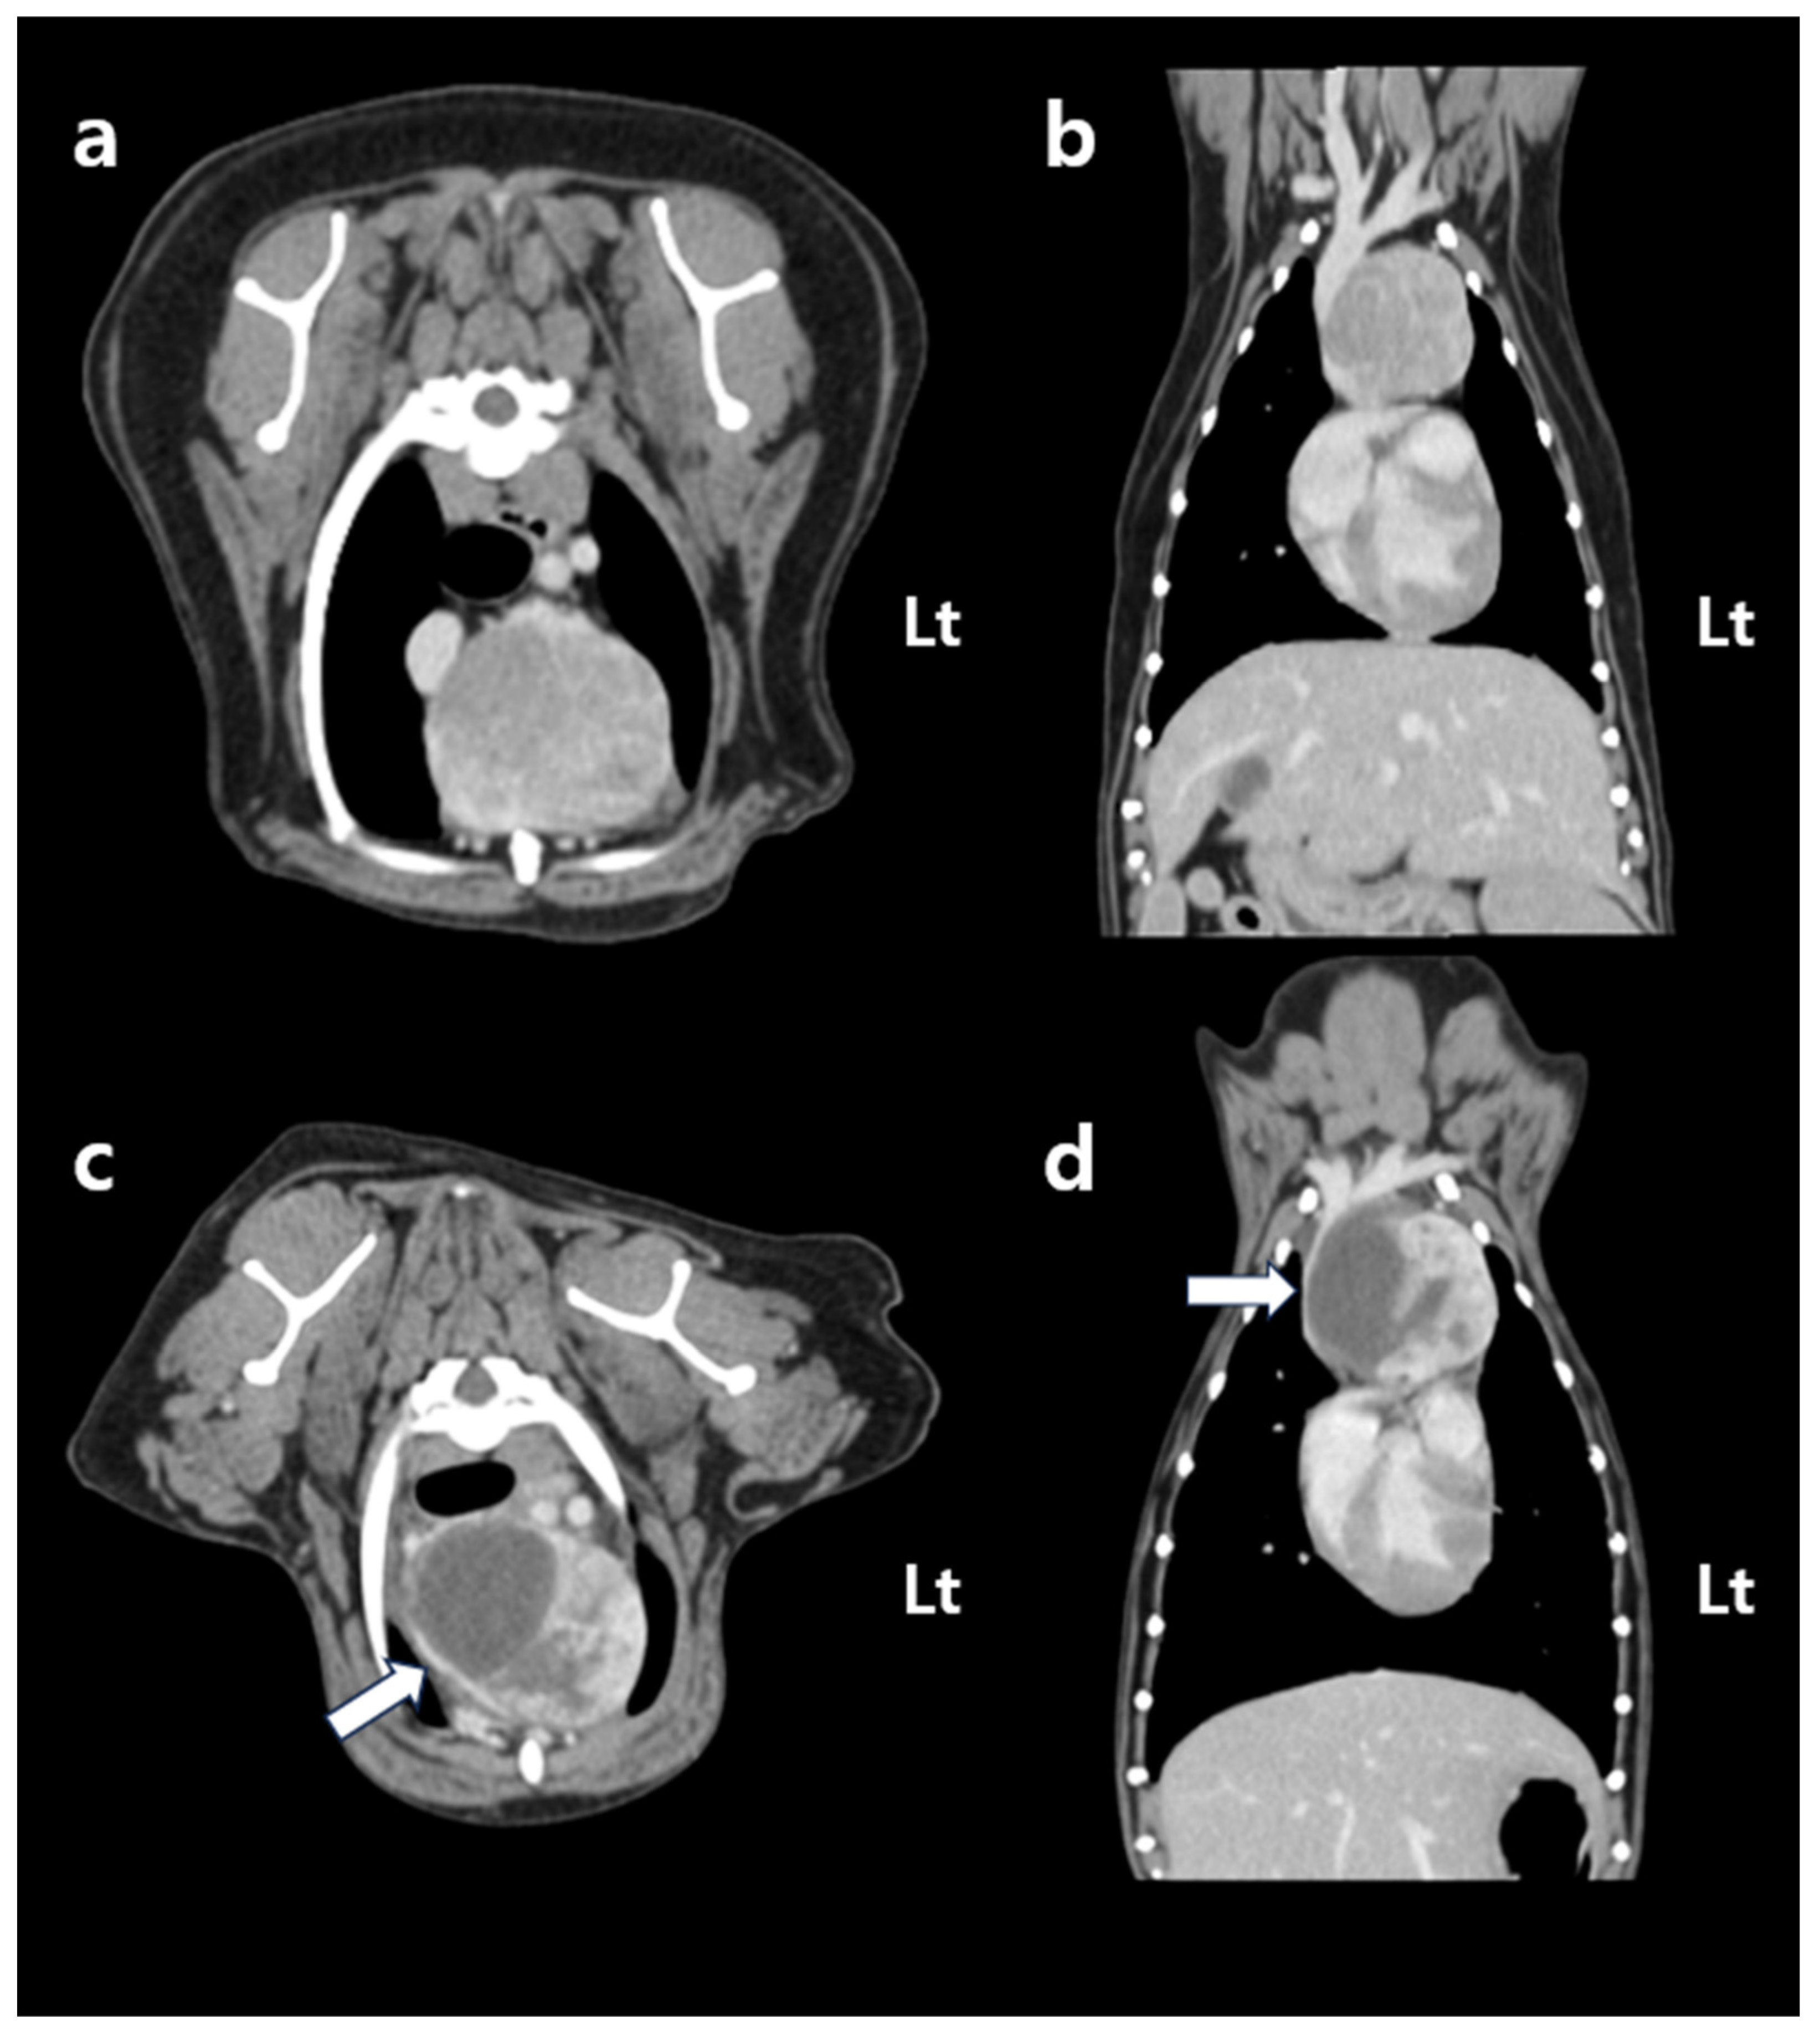

A 10-year-old intact male Pomeranian dog was incidentally found to have a cranial mediastinal mass during a routine checkup. No relevant past medical conditions were reported. According to the owner, there was no known family history or genetic predisposition. The dog lived indoors as a companion animal and exhibited no behavioral abnormalities or notable psychosocial stressors. Physical examination revealed a body weight of 6.4 kg, with no abnormalities detected in vital parameters or thoracic auscultation. Thoracic radiographs demonstrated a round, soft tissue opacity mass within the cranial mediastinum. Complete blood count (CBC) results were within normal limits, with platelet count (262 × 103/μL; reference range: 200–500 × 103/μL), red blood cell count (7.51 × 106/μL; reference range: 5.5–8.5 × 106/μL), hemoglobin (16.6 g/dL; reference: 12–18 g/dL) and hematocrit (49.7%; reference: 37–55%). Pre-contrast thoracic computed tomography (CT) revealed a round, soft tissue-attenuating mass (length: 34.3 mm; width: 35.6 mm; height: 31.2 mm) located within the cranial mediastinum. Intravenous administration of iodinated contrast medium revealed that the mass demonstrated heterogeneous contrast enhancement. The lesion was immediately adjacent to the cranial vena cava, right atrium, and right ventricle; however, no evidence of invasion into adjacent cardiovascular or thoracic structures was observed, and no compressive effect on the vasculature was identified. Thoracic lymph nodes were within normal limits, and no evidence of metastatic disease was identified. Pre- and post-contrast CT evaluation revealed no abnormalities of the thyroid glands, which were normal in size and morphology. Incidental findings included benign prostatic hyperplasia consistent with the patient’s intact male status, as well as urinary bladder calculi and a small renal cortical cyst.

Two weeks later, a CT scan was acquired for radiation therapy planning. The dog was positioned in ventral recumbency using a custom-made vacuum immobilization cushion (Chunsung, Seoul, Republic of Korea). Whole-body pre- and post-contrast CT images were obtained using a 64-multi-slice helical CT scanner (Optima CT660; GE HealthCare, Chicago, IL, USA) with the following parameters: 120 kVp, 160 mA, and 1.25 mm slice thickness. Intravenous contrast enhancement was achieved by administering 600 mg iodine/kg of iohexol (Omnipaque™ 300, GE HealthCare), using a power injector (MEDRAD® Stellant, Bayer, Leverkusen, Germany). No significant changes in mass size, morphology, or contrast enhancement pattern were observed compared to the previous CT scan (Figure 1a,b).

At follow-up, the dog remained in a stable condition, with normal respiratory function and no recurrence of swelling in the submandibular or axillary region. Follow-up CT was performed on day 33 post-SBRT (37 days after the first fraction of SBRT), not primarily to assess tumor shrinkage but rather to evaluate potential treatment-related complications. Specifically, the scan was intended to monitor for tumor-associated hemorrhage and hematoma formation, to assess compression of adjacent vascular and mediastinal structures, and to rule out bleeding from surrounding normal organs. The CT showed an overall increase in tumor dimensions (length: 42.1 mm; width: 49.0 mm; height: 40.0 mm). Tumor volume increased from 25.0 cm3 to 46.4 cm3; however, the contrast-enhancing portion decreased by approximately 25% to 18.7 cm3. This decrease was accompanied by a relative increase in the non-enhancing component of the mass (pre-contrast: 30 HU; post-contrast: 31.5 HU), which exerted compression on the cranial vena cava (Figure 1c,d). Based on imaging features, hematologic findings, and the clinical course, the non-enhancing region was interpreted as a tumor-related hemorrhage secondary to radiation therapy. Thoracic radiography performed on day 88 post-SBRT (92 days after the first fraction of SBRT) revealed a further reduction in the mediastinal width to 43.4 mm, with no evidence of pleural effusion (Figure 4). The dog remained clinically stable, without any evidence of dyspnea, lethargy, or other signs of anemia. At the last follow-up on day 143 after the first SBRT fraction (139 days after completion of the final fraction), the patient was still clinically stable without recurrence of dyspnea or anemia-related signs. Thoracic radiographs at that time showed no significant changes compared with those obtained on day 88 post-SBRT (Figure 4c).

Figure 1. Post-contrast CT images acquired before (a,b) and 37 days after (c,d) the first fraction of stereotactic body radiotherapy. Transverse images are shown in (a,c), and dorsal reconstructions are shown in (b,d). All images were obtained using a soft tissue algorithm (window level, 45; window width, 450). Before stereotactic body radiotherapy, the cranial mediastinal mass displays heterogeneous contrast enhancement and is located in close proximity to the cranial vena cava, right atrium, and right ventricle. CT performed 37 days after the first radiation fraction shows that the overall size of the mass has increased; however, the volume of the contrast-enhancing region has decreased by approximately 25%. The cranial vena cava is compressed by a newly developed non-enhancing region (white arrow). CT, computed tomography. Lt: left.